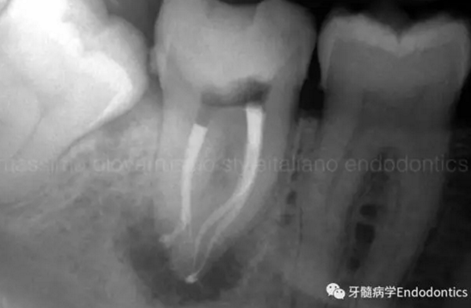

圖6.術后X線片顯示在根管機械預備后保留了原始的根管解剖形態(tài)結構。冠方預敞和探查保證了對整個根管解剖形態(tài)結構的保護。